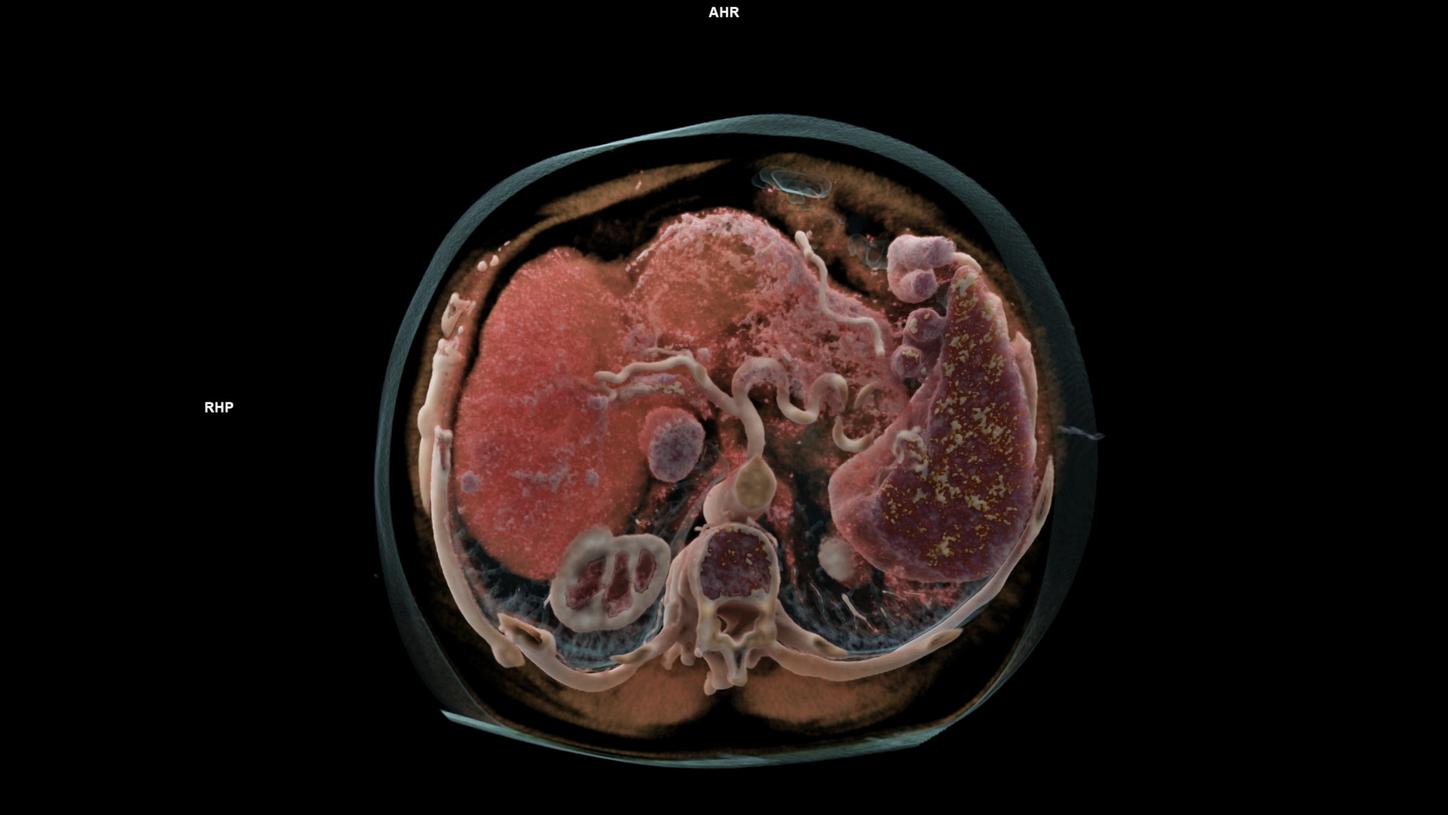

- AI-based automated image analysis

- MRI / CT

- PET-CT / SPECT